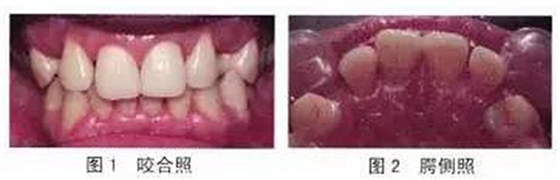

既往史:患者9歲換牙時(shí)在某診所將雙側(cè)恒尖牙誤拔而保留了乳尖牙,23歲時(shí)因乳尖牙松動,又將其拔除。系統(tǒng)病史:無高血壓、心臟病、糖尿病等。檢查:13、23缺失,粘膜無紅腫,牙槽嵴豐滿,無骨突。14、12、22、24牙體無缺損,無松動,牙周狀況良好。12、11間有約1 mm間隙。覆牙合、覆蓋關(guān)系正常(如圖1~2)。